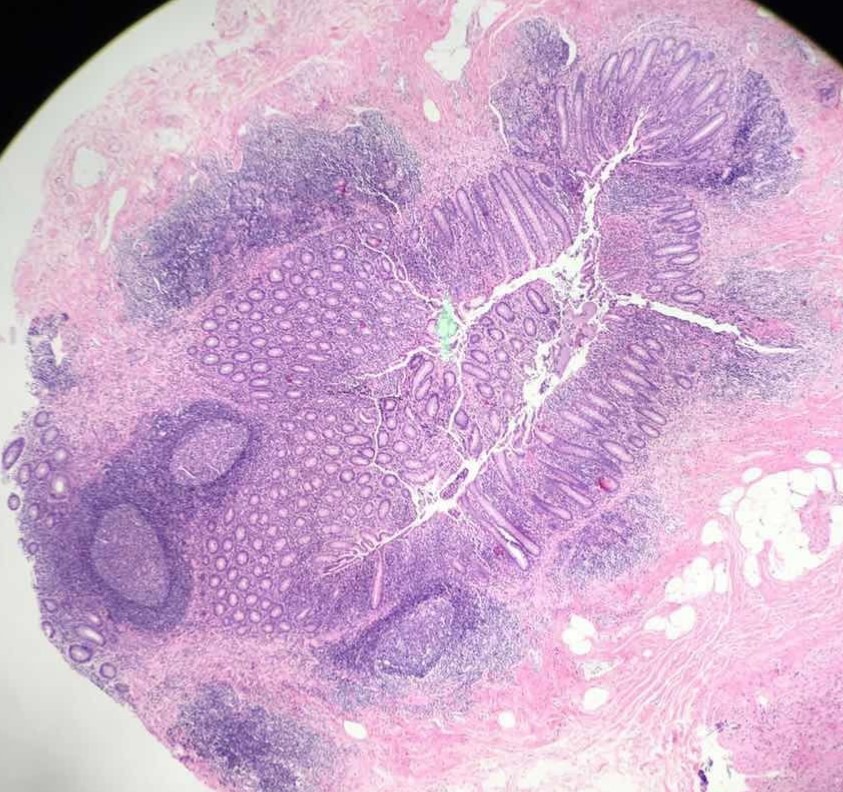

医生阅片:病理医师将染色后切片在显微镜下观察,通过组织细胞的形态学变化对送检标本做出相应病理诊断。阅片通常分两级阅片,需由病理科住院医师和主治医师承担,然后经过报告上的双签字确认,得出最终诊断结果。由于可以在显微镜放大下分辨1微米水平的细胞变化,所以病理诊断是目前公认的对疾病最可信赖的定性诊断,是B超、CT、生化等手段所不能代替的。

(注:病理医师在显微镜低倍与高倍镜下观察到的两张不同病理切片的图像)